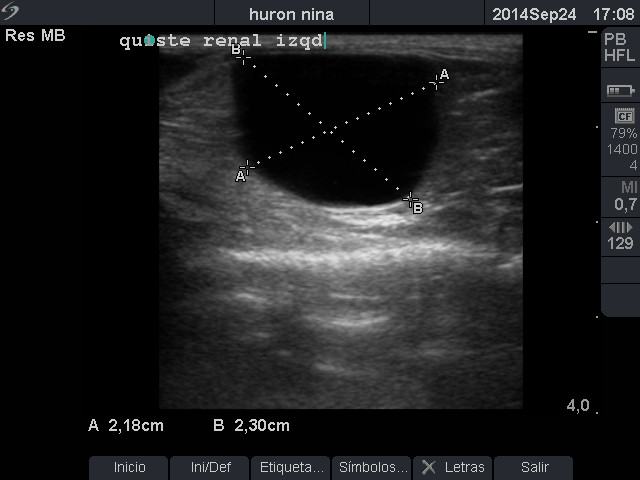

En el estudio del riñón izquierdo se observa pérdida de morfología ecográfica renal con presencia de estructura ovalada de paredes finas y contenido anecogénico compatible con posible quiste renal.